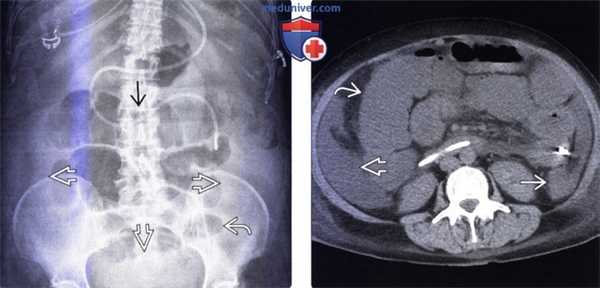

(Слева) На рентгенограмме в положении лежа на спине, выполненной женщине 63 лет, недавно перенесшей операцию по поводу вентральной грыжи, определяется диффузное расширение толстой кишки, при этом какого-либо расширения тонкой кишки не выявлено.

(Справа) На КТ у этой же пациентки визуализируется открытая рана после оперативного вмешательства по поводу грыжи. Толстая кишка диффузно расширена, в то время как тонкая кишка имеет нормальный поперечный размер. Расширение просвета толстой кишки сохраняется вплоть до прямой, хотя нисходящая ободочная кишка расширена в меньшей степени, что часто имеет место при илеусе, и не должно наводить на ошибочную мысль об обструкции.